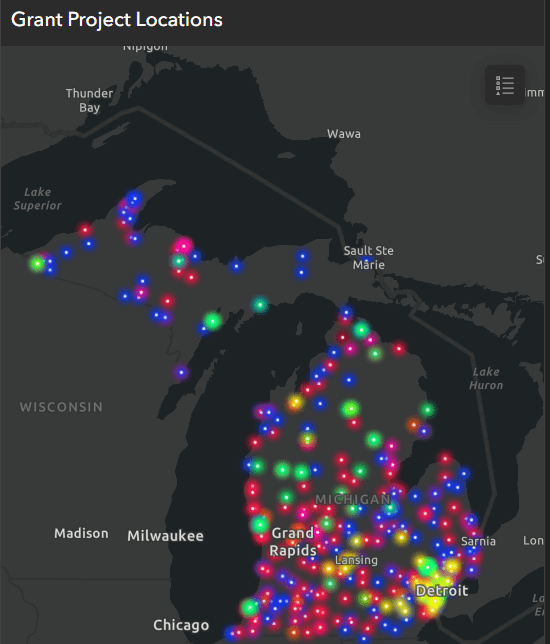

MR angiograms (top row) of the right coronary arteries in two persons living with HIV (PLWH) show location of cross-section (dotted lines) of coronary vessel wall image (bottom row) and the corresponding automatic wall thickness measurement. (A) Image from 50-year-old male PLWH with increased coronary vessel wall thickness of 1.5 mm and grade 1 diastolic dysfunction. (B) Image from 52-year-old male PLWH with coronary vessel wall thickness of 1.2 mm and normal diastolic function.

Researchers at the National Institutes of Health (NIH) set out to assess early coronary atherosclerosis burden, and its relation to how the heart is functioning, in people living with HIV who were asymptomatic and had low cardiovascular disease risk. For the study, the researchers recruited 74 adults (mean age of 49 years) living with HIV without known cardiovascular disease and 25 matched healthy controls (mean age of 46 years). Controls were negative for HIV and were required to be healthy with no known significant medical conditions, including coronary disease. All underwent MRI to measure coronary vessel wall thickness and an echocardiogram to assess left ventricular function.

The results showed increased coronary vessel wall thickness in the HIV group, compared to controls. The increased coronary artery vessel wall thickness was independently associated with elevated left ventricular mass index and impaired diastolic function.